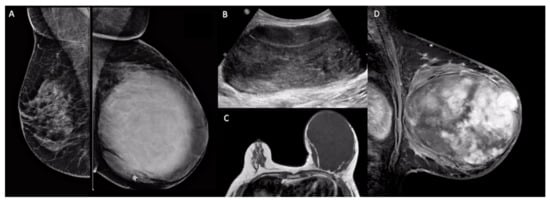

4. Hereditary Genetic Features